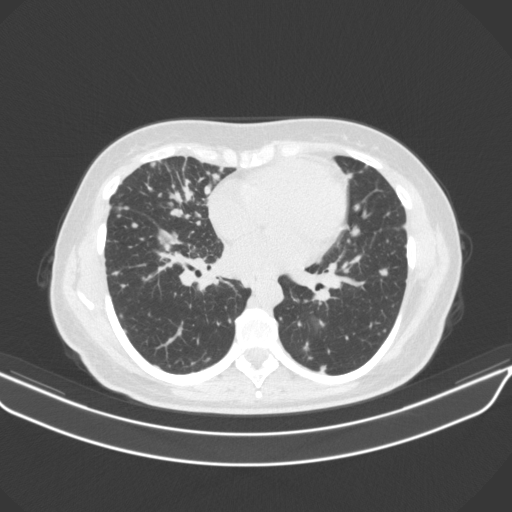

Generated VENOUS CT scan (A→B translation)

Full window (WL 1023.5, WW 4095 β†’ Low βˆ’1024, High +3071)

Lung window (WL -600, WW 1500 β†’ Low βˆ’1350, High +150)

Mediastinum window (WL 40, WW 400 β†’ Low βˆ’160, High +240)